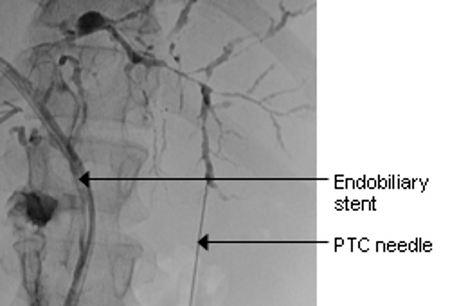

Magnetic resonance cholangiopancreatography (MRCP)/MRI to look for biliary disease or pancreatic duct disease. If relevant strictures are identified in the setting of alarm symptoms, endoscopic ultrasonography or endoscopic retrograde cholangiopancreatography (ERCP) should be carried out in order to obtain more imaging information and to take tissue specimens for cytological examination.[55][56] For extra-hepatic strictures, endoscopic ultrasound-guided tissue acquisition may be preferred over ERCP.[57][Figure caption and citation for the preceding image starts]: Typical endoscopic retrograde cholangiopancreatography (ERCP) findings in a patient with primary sclerosing cholangitis (PSC): multifocal strictures of the intra- and extrahepatic bile ductsCourtesy of Dr Kris Kowdley; used with permission [Citation ends].